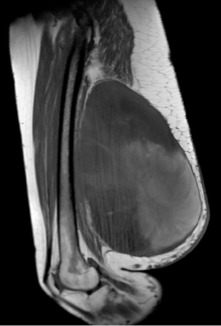

Lipossarcoma: este tipo de câncer é originado do tecido gorduroso do corpo, frequente em pacientes adultos e idosos. A localização mais frequente é a coxa, seguido dos demais membros e retroperitônio. Tem o aparecimento insidioso podendo atingir grandes volumes, merece atenção especial devido ao alto potencial de metástases à distância.